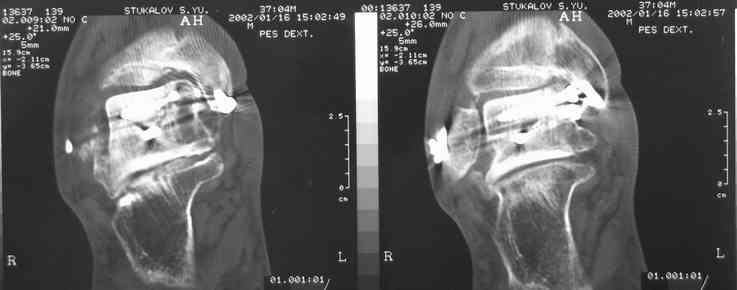

И второй случай из недавней ташкентской практики, (извините за качество ренгенограммы и только в одной проекции) случай падения с высоты (кстати моего друга - известного киноактера) - открытый

смещенный перелом тарана, с переломом переднего края дистального эпиметафиза большеберцовой кости.

При поступлении в приемной сделана первичная обработка с ушиванием открытой латеральной раны и вытяжением за пятку.

Из-за отсутствия времени пришлось оперировать на второе утро, из материала, что имеем на месте, фиксирован двумя шурупами, а третий-это контур сломанного жойстика в 4 мм. На дистальный медиальный конец тибиа antiglide 3.5 мм пластина. Через пару дней выписан и несмотря на предупреждение, самостоятельно начал нагрузку в 4 недели, время не ждет, снимается в боевике в Росийской Федерации.

Djoldas Kuldjanov, MD